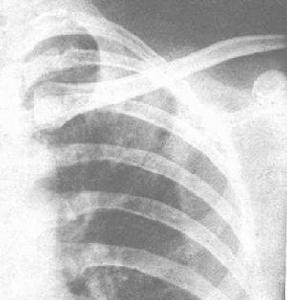

克雷白桿菌屬感染1.呼吸道感染 肺炎克雷白桿菌是呼吸道感染最常見的致病菌之一。在痰標本所得革蘭陰性桿菌中占第二位,僅次於銅綠假單胞菌國外報告有的占首位。醫院內交叉感染常導致細菌在咽部寄殖繼引起支氣管炎或肺炎。長期住院、套用抗菌藥物等使患者咽部肺炎桿菌細菌下行而引起支氣管及肺部感染。肺炎克雷白桿菌引起的急性肺炎與肺炎鏈球菌肺炎相似起病急,常有寒戰高熱、胸痛、痰液黏稠而不易咳出痰呈磚紅色或深棕色(25%~50%),也可為血絲痰和鐵鏽色痰。部分患者有明顯咯血體檢可發現患者呈急性面容、呼吸困難、發紺,少數患者可出現黃疸、休克。2/3患者體溫在39~40℃間,口唇皰疹不常見,肺部有實變體徵,有濕性囉音。X線表現多變可有大葉實變、小葉浸潤和膿腫等表現大葉實變多位於上葉,由於炎症滲出液多而黏稠,故葉間裂常呈弧形下墜。炎症浸潤也比其他肺炎濃密,邊界銳利,16%~50%的患者有肺膿腫形成。少數呈支氣管肺炎或兩側肺外周浸潤,有時也可呈兩側肺門旁浸潤。本病早期即常有全身衰竭,預後較差,病死率約50%,發生廣泛肺壞疽者則預後更差。肺炎克雷白桿菌肺炎可表現為慢性病程,也可由急性延續成慢性,呈肺膿腫、支氣管擴張與肺纖維化的臨床表現。

典型的肺炎克雷白桿菌肺炎常發生於中老年男性、長期飲酒的慢性支氣管肺病患者,有較典型的臨床表現和X線徵象,結合痰培養結果,不難診斷。但在有嚴重原發疾病基礎上的發病者,臨床表現多不典型,診斷較為困難。凡在原有疾病過程中出現高熱、白細胞和中性粒細胞增多X線胸片上出現新的浸潤病灶而青黴素治療無效者應考慮本病。連續2次或2次以上痰培養陽性,或胸腔積液血培養陽性可以確診多數敗血症患者的白細胞總數明顯增多嗜中性粒細胞增高;但血液病患者或用抗代謝藥物者白細胞數可不增加或反有減少。其他如尿路感染及腦膜炎患者的尿液及腦脊液均有相應變化。確診應根據細菌培養結果。 鼻硬結亞種所致慢性肉芽腫性硬結症,活組織檢查中找到Mikulicz細胞具確診價值。

白細胞和中性粒細胞增多,X線胸片上出現新的浸潤病灶而青黴素治療無效者應考慮本病。連續2次或2次以上痰培養陽性,或胸腔積液、血培養陽性可以確診多數敗血症患者的白細胞總數明顯增多,嗜中性粒細胞增高;但血液病患者或用抗代謝藥物者白細胞數可不增加或反有減少。其他如尿路感染及腦膜炎患者的尿液及腦脊液均有相應變化。

X線胸片上出現新的浸潤病灶。